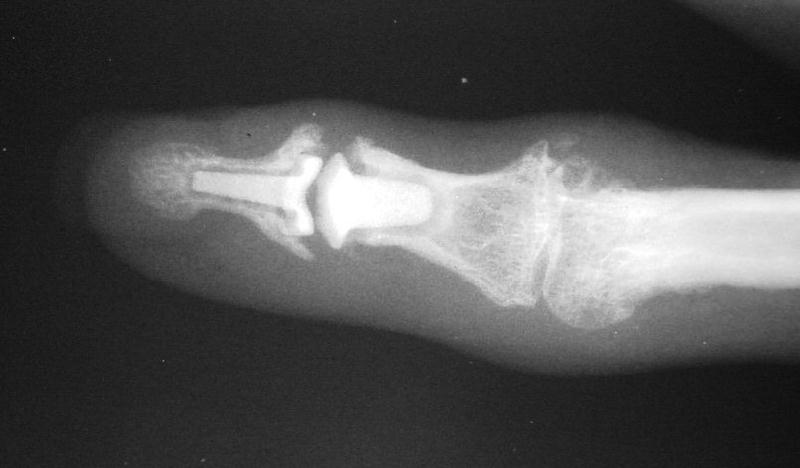

The trial implant sizer shows the true size of the implant. The final implant has a radiolucent coating  which makes it appear smaller than it is on Xray.

Final implant radiographs.